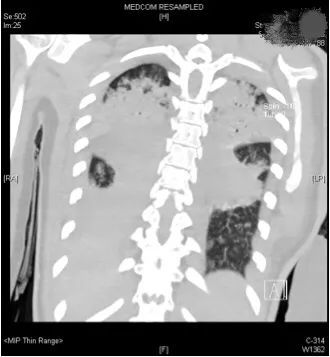

高烧三天退不下来,1月9日,小文来到浙江省中医院下沙院区就诊,因为高热不退,CT检查提示

肺部有小片状炎症表现,这意味着肺部有明显感染,接诊的医生立刻安排她住院治疗。

(小文转入ICU治疗 医院供图)ICU主任王灵聪说,“病人转过来后,我们第一时间给予气管插管呼吸机辅助通气治疗,并复查了肺部CT,痰液培养、血液培养等各种标本培养,全面评估病情,确定治疗方案。”

评估结果不容乐观,呼吸机的支持水平要求很高,100%纯氧条件下小文体内的氧分压才勉强达标,持续高烧超过40摄氏度,CT复查提示两肺几乎全部实变,炎症指标非常高。

(小文的影像检查显示,双肺几乎完全实变)如果病情再继续恶化下去,就需要上ECMO(体外膜肺氧合机)了。